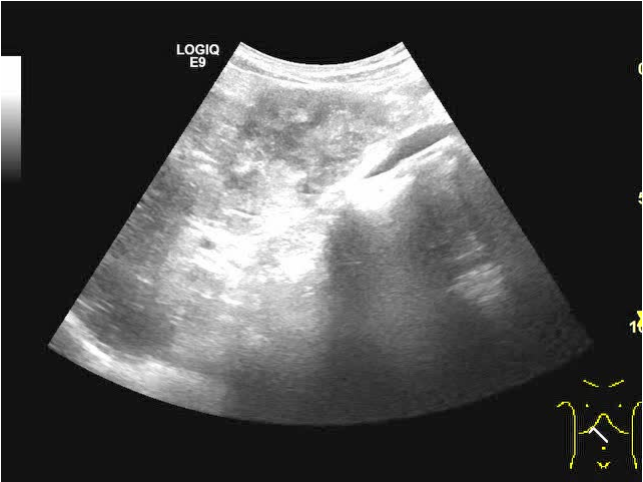

半月前他院超声检查结果:

超声检查所见:

超声所见: